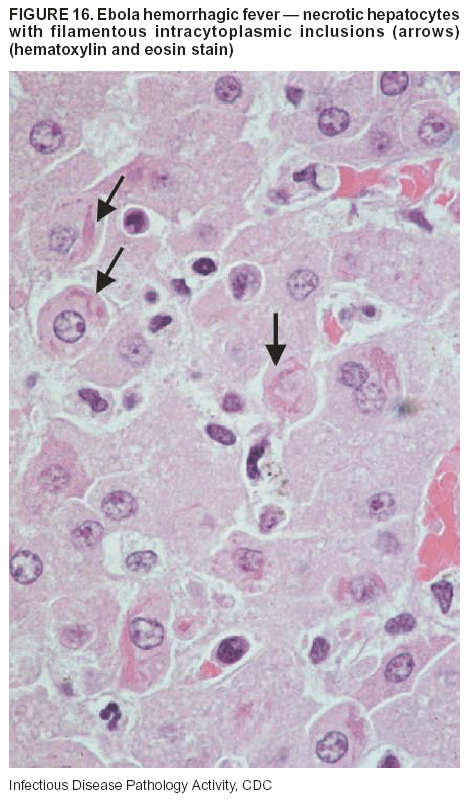

Pathologic Findings. The term viral hemorrhagic fever is reserved for febrile illnesses associated with abnormal vascular regulation and vascular damage. Common pathologic findings at autopsy include petechial hemorrhages and ecchymoses of skin (Figure 15), mucous membranes, and internal organs. Although systemic hemorrhages occur in the majority of viral hemorrhagic fevers, certain agents infect specific cells and thus histopathologic features can differ among agents. Necrosis of liver and lymphoid tissues, as well as diffuse alveolar damage, occur in the majority of viral hemorrhagic fevers, but can be more prominent for certain infections (e.g., midzonal hepatocellular necrosis is prominent in yellow fever, but not in dengue). Viral inclusions can be visualized in hepatocytes with Ebola or Marburg infections by using light and electron microscopy (Figure 16) (49--54).

Diagnostic Specimens. Performing a complete autopsy with histologic sampling of multiple organs can determine the extent of the disease and help identify the specific virus. After a specific etiologic agent has been isolated or identified from an index case, targeted sampling of additional cases with similar symptoms can decrease the exposure of autopsy personnel to these hazardous agents and still yield diagnostic material. For example, during outbreaks of Ebola hemorrhagic fever in Africa, using IHC on skin punch biopsy samples was sufficient to provide a diagnosis in a substantial number of fatalities and minimized the risk to the medical personnel who obtained the specimens (49).